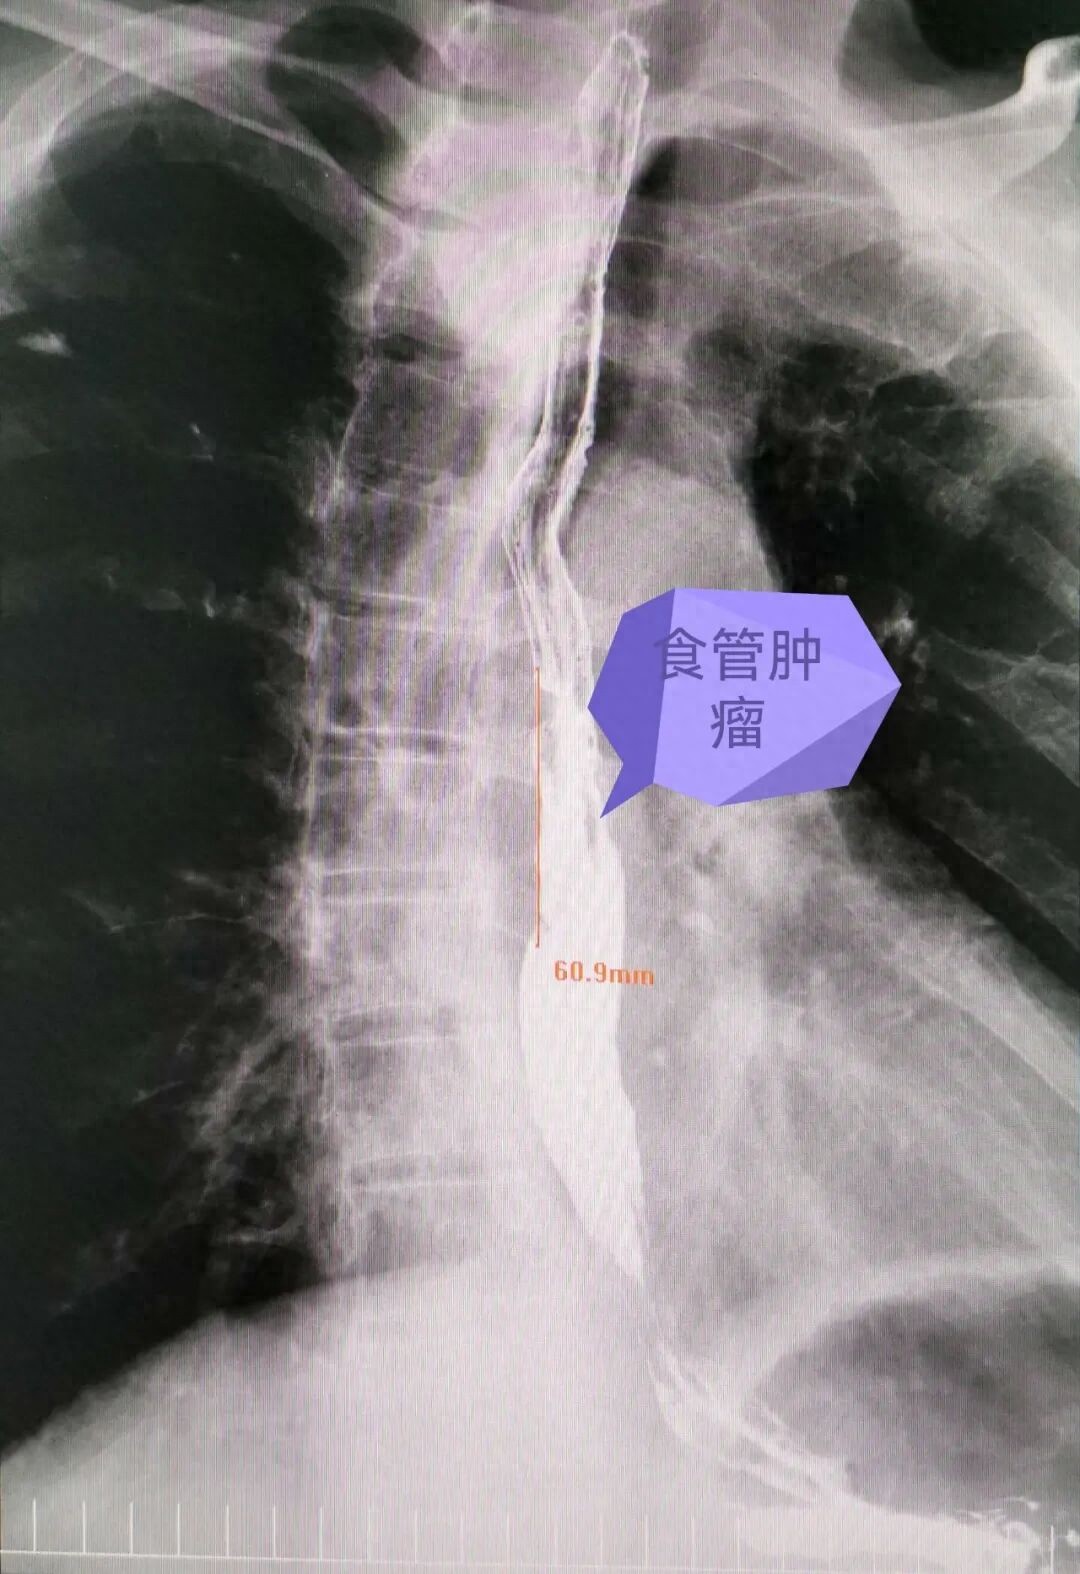

术前食管钡餐造影图片

术前胸部CT图片术前胃镜、胸部CT及食管钡餐造影各项辅助检查:提示肿瘤位于胸中下段食管,大小约6×4×3cm。胸腹部增强CT:脊柱旁腰升静脉、奇静脉及半奇静脉扩张,腰2椎体水平下腔静脉与右侧椎外静脉丛相通,且明显增粗。患者抽烟数十年,平素咳嗽痰多,痰液细菌培养:致病菌存在。呼吸科会诊考虑:1.慢性阻塞性肺病;2.I型呼吸衰竭;3.肺气肿合并肺大疱;4.肺部感染。副主任医师梁艳盆给予常规呼吸功能训练、雾化祛痰、抗感染等措施改善肺功能,经过术前准备患者达到手术条件。术前,主任医师王晓民针对奇静脉扩张血管畸形特殊病例查阅相关文献,并带领小组进行详细讨论,严密制定手术方案。为避免因术中切断奇静脉弓引起血管畸形改变发生严重的循环障碍危及生命,特别强调必须保留奇静脉弓。在与患者及家属充分沟通确定手术方案并告知手术风险及可能发生的各项并发症后,在全麻下开展胸腹腔镜联合食管癌根治左颈部吻合术。术中游离食管肿瘤及清扫淋巴结